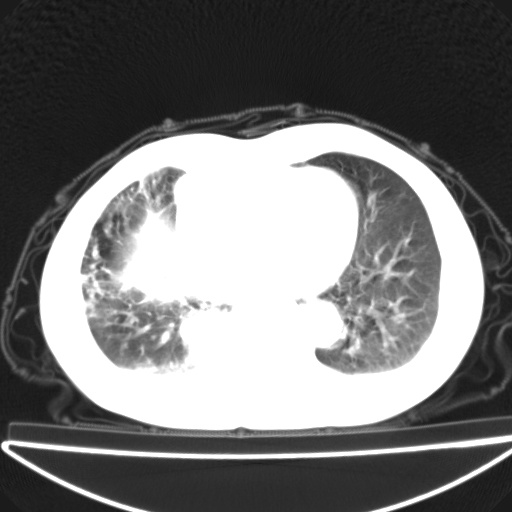

以下是引用jsgdoctor在2008-11-6 22:12:00的发言:[br]右主支气管壁明显增厚,管腔狭窄.考虑为右侧中央型肺癌伴阻塞性炎症\\肺脓肿.

以下是引用zjzjr在2008-11-6 20:25:00的发言:[br]中心型肺ca,合并阻塞性肺炎

以下是引用zsl6918在2008-11-6 19:43:00的发言:[br]右侧中心性肺癌(鳞癌)